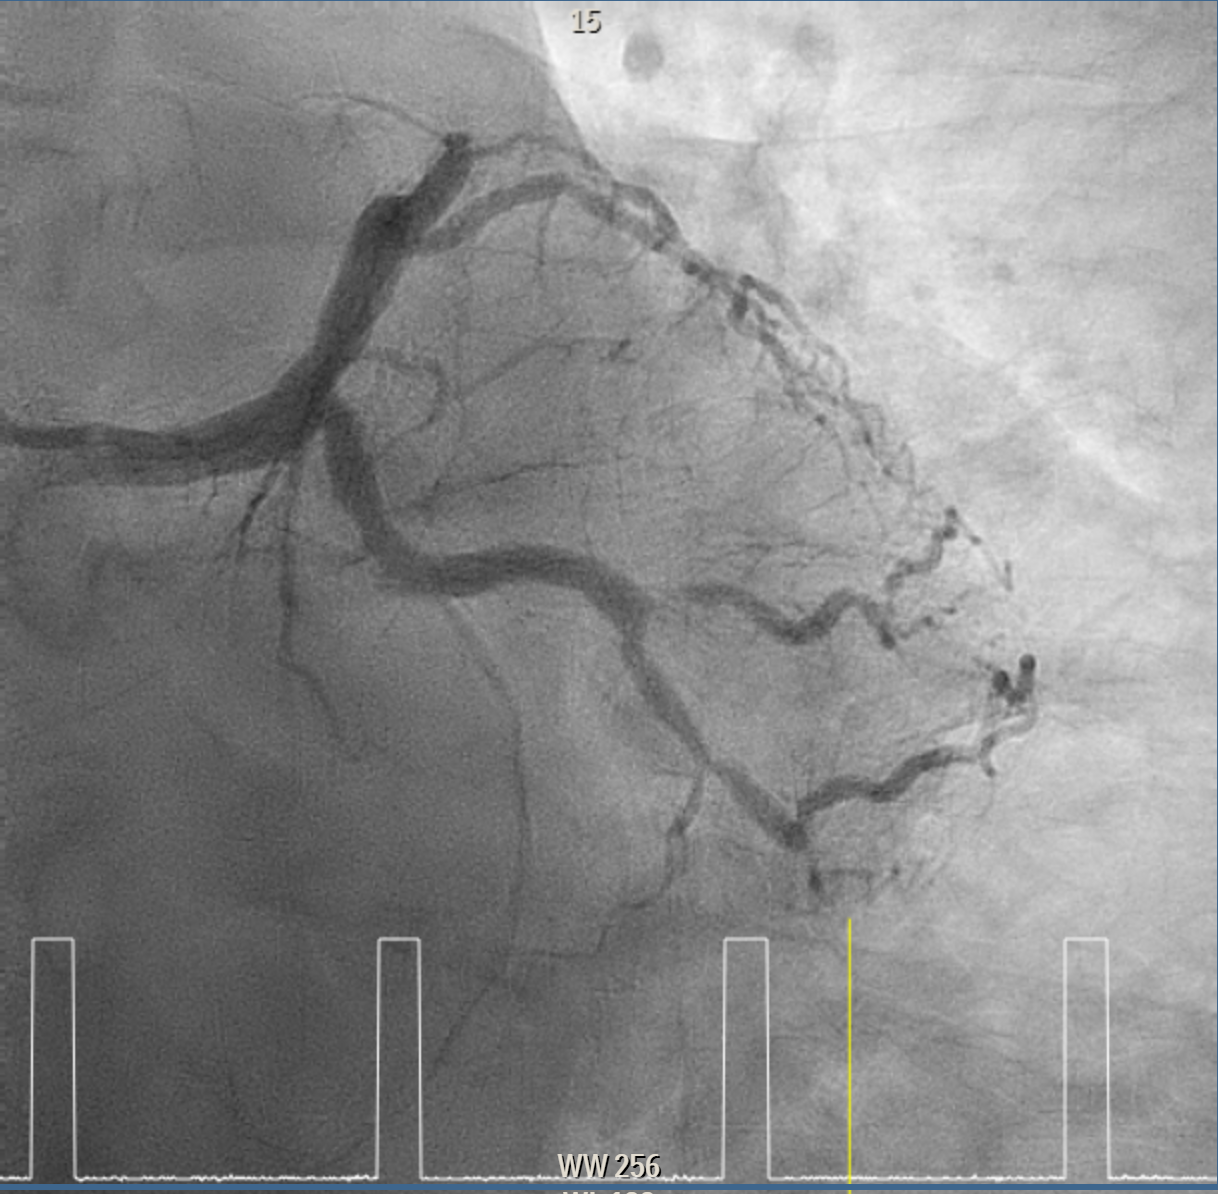

Coronary intervention was performed on a proximal LAD (pLAD) total occlusion via single right radial approach using 6F XB 3.5 guiding catheter. Initial antegrade attempts with RunThrough Floppy and Fielder-XT wires were unsuccessful due to buckling against the proximal cap. Wire strategy was escalated to Gaia Second wire with Finecross microcatheter support, allowing careful penetration of proximal cap and subsequent advancement through distal cap. True lumen position was confirmed with contrast injection through the microcatheter, and wire was then exchanged to a Fielder-XT wire to safely navigate to distal LAD (dLAD) and reduce risk of perforation. Lesion preparation was performed with stepwise predilatation, beginning with Sapphire 0.85 ¡¿ 5 mm balloon at 10–12 atm in pLAD to dLAD. Further predilatation was performed with Sapphire 2.0 ¡¿ 15 mm balloon at 12 atm from dLAD to mid LAD (mLAD) and higher pressure up to 16atm at pLAD. Despite multiple inflations, pLAD remained tight, prompting escalation with a Sapphire 2.5 ¡¿ 15 mm balloon at up to 18 atm and Scoreflex NC 3.0 ¡¿ 15 mm balloon at 8–12 atm to adequately prepare mildly calcified pLAD segment. Final predilatation achieved optimal luminal caliber. DCB was then performed, with m-dLAD treated using Magic Touch 2.25 ¡¿ 35 mm and the p-mLAD treated with Magic Touch 3.0 ¡¿ 40 mm. Both were deployed at 8 atm for 60 seconds. The procedure resulted in excellent luminal gain with no residual stenosis, recoil, or perforation.